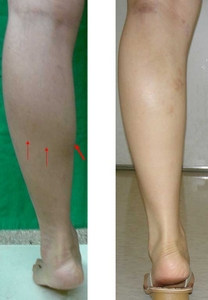

大家可以輕易看到圖中紅色箭頭所指的, 就是您腿部美麗的致命傷{上圖裏小腿圍高達39.5cm}. 而小腿神經整形最大的幫助, 就在於使您可以軟化腿部曲線(使得內側緋腸肌永久軟化 + 逐漸萎縮), 不再有激突點, 和一坨硬肉說拜拜!!

圖左, 踮腳尖時非常激突; 圖右為神經整形手術後一個月, 即使踮腳尖, 也不再出現恐怖的硬肉球!!

圖左, 踮腳尖時非常激突; 圖右為神經整形手術後一個月, 即使踮腳尖, 也不再出現恐怖的硬肉球!!

圖右: 經過小腿抽脂與神經整形術後半年, 即使墊腳尖, 肌肉收縮邊緣陰影(紅色箭頭)已經消失, 內側更為筆直, 腿圍小兩公分.

圖右: 經過小腿抽脂與神經整形術後半年, 即使墊腳尖, 肌肉收縮邊緣陰影(紅色箭頭)已經消失, 內側更為筆直, 腿圍小兩公分.